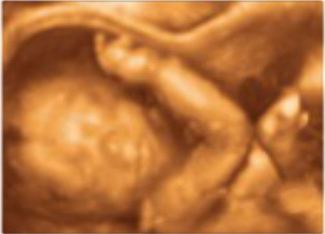

Selección de Sexo

Es la práctica mediante la cual se elige el sexo del bebé antes de la implantación por medio de técnicas de alta tecnología con fines médicos.